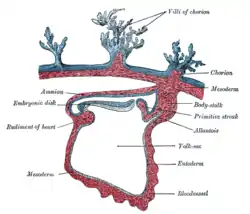

Micrograph showing chorionic villi. Very high magnification. H&E stain. Section through the embryo.

Section through the embryo. Transverse section of a chorionic villus.

Transverse section of a chorionic villus. Human embryo of about 28 days, with yolk-sac.

Human embryo of about 28 days, with yolk-sac.